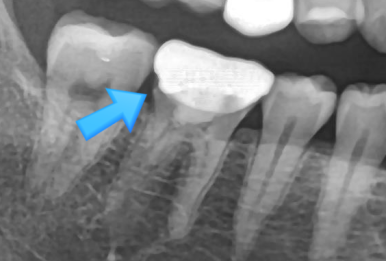

정밀 검진 결과,

하악 어금니(#36, #46) 부위에서

보철 경계의 착색과 미세 틈이 관찰되었습니다.

보철 내부 우식 의심도 있었기에

기존 금니를 제거하고 내부를 확인했습니다.